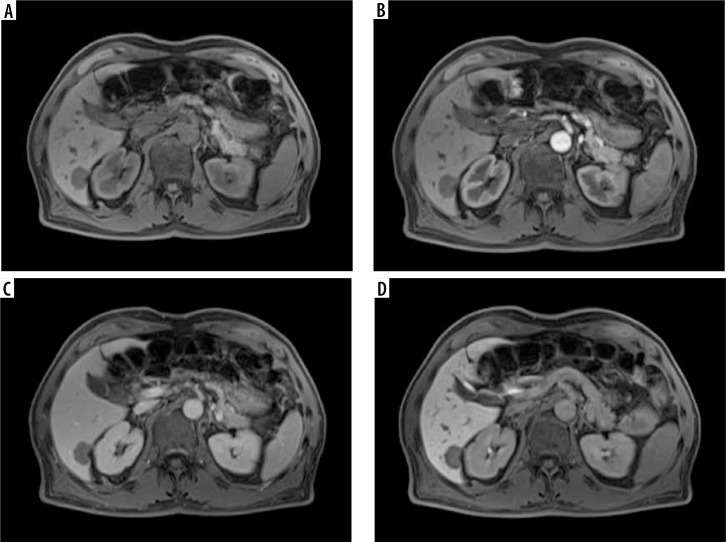

Abstract Image